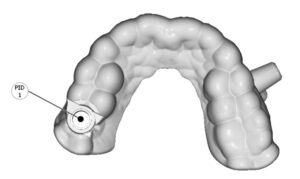

En nuestro Centro radiológico dental, contamos con equipamiento de vanguardia para ofrecerte los mejores resultados en radiografías dentales, radiografías panorámicas dentales, tomografía dental 3D y muchas más. Nuestro equipo de odontólogos está capacitado para brindarte la mejor atención para que tu dentista pueda tomar decisiones informadas sobre tu tratamiento. Además, nuestra radiología digital dental garantiza imágenes de alta calidad y reducción de daños por radiación. Si necesitas una radiografía panorámica dental, no dudes en visitarnos. Contáctanos para conocer nuestros precios y horarios de atención.